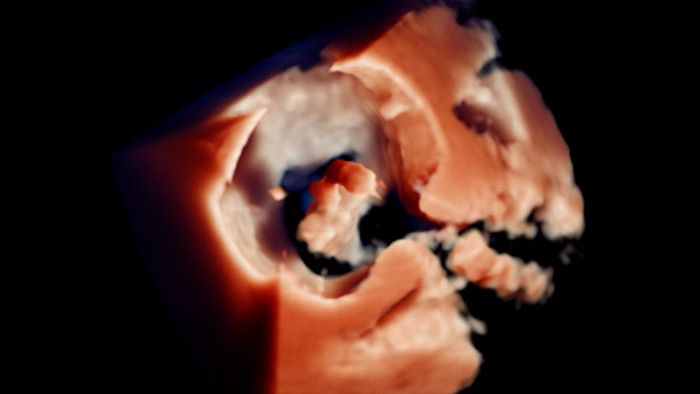

Segmentación del modelo EchoNavigator 3D

Reproducción con TrueVue con zoom 3D para LAA con visualización MultiVue

Visualización TrueVue de la valvulopatía mitral de extremo a extremo